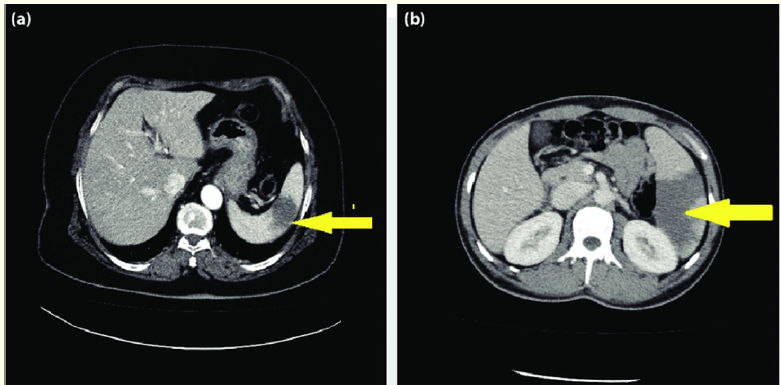

Leiomyosarcoma of the Inferior Vena Cava Diagnosis and Treatment: Case Report

O Belmaachi, K Farahi, S Lyazidi, A Adaoui, O El Allam and Y Ettaoumi